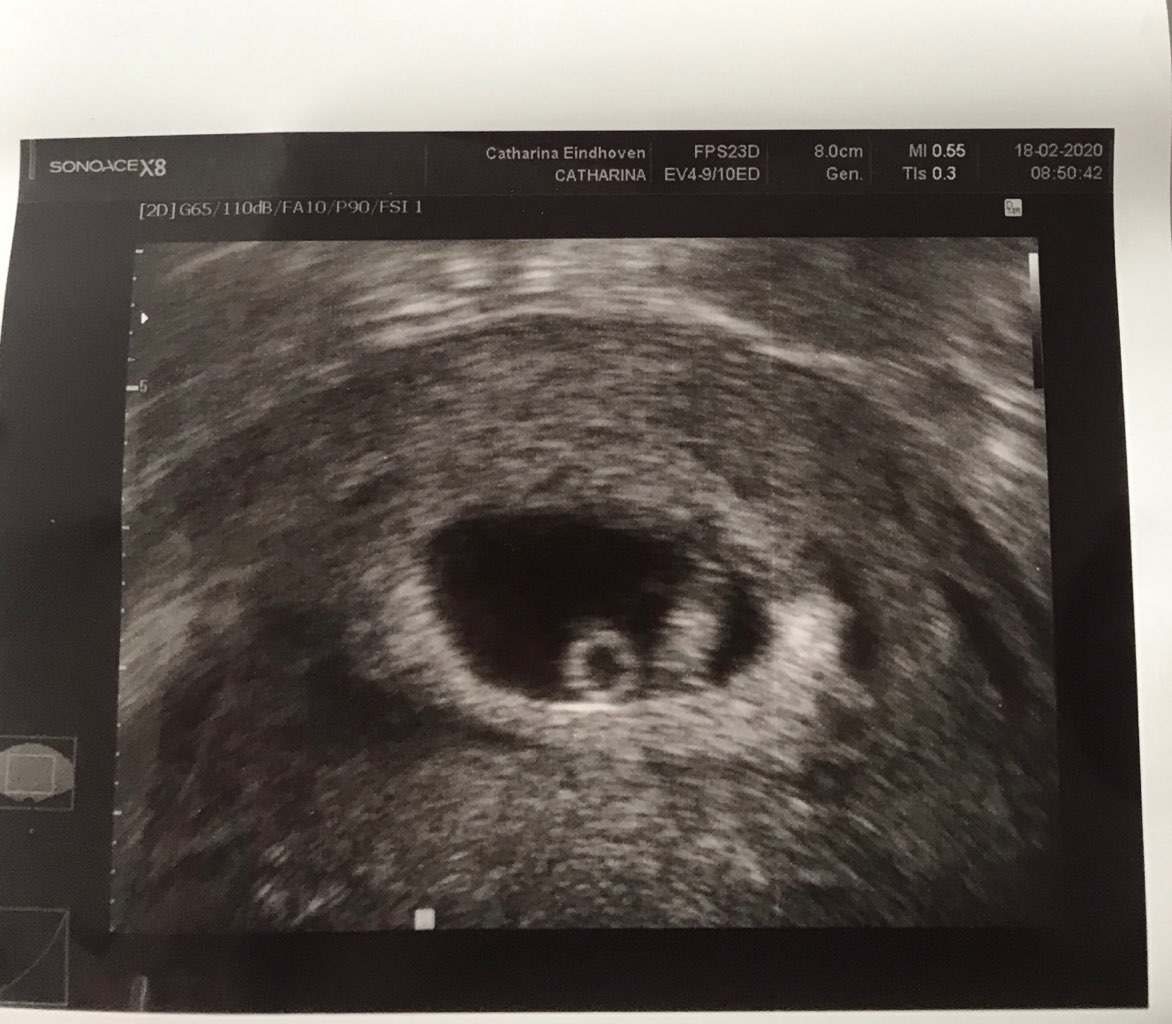

Pomiędzy tymi dwoją usg jest tydzień różnicy 26dpt i 33dpt na drugim widać już zdecydowanie ładnie pecherzyk zoltkowy i zarodek z sercem

• IMG_1903.jpeg

IMG_1903.jpeg

146,1 KB · Wyświetleń: 68